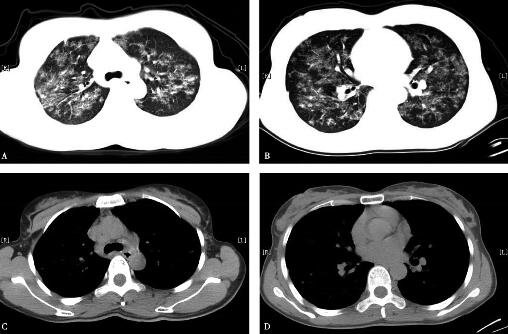

7.胸部高分辨CT(2008年12月25日):双肺纹理增多紊乱,双肺弥漫磨玻璃、斑片、结节影,密度不均匀,边界欠清,部分沿支气管血管束分布,纵隔内见多个增大淋巴结,双侧肺门正常,双侧胸腔内未见积液(图1)。

图1